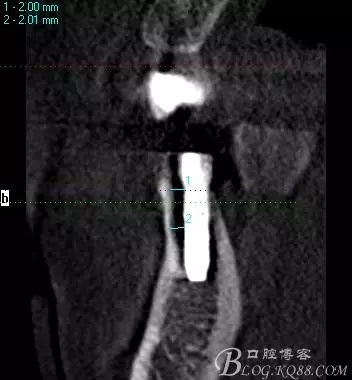

術(shù)后片 能顯示間隙沒有植骨是空的

術(shù)后片顯示植入情況都可以